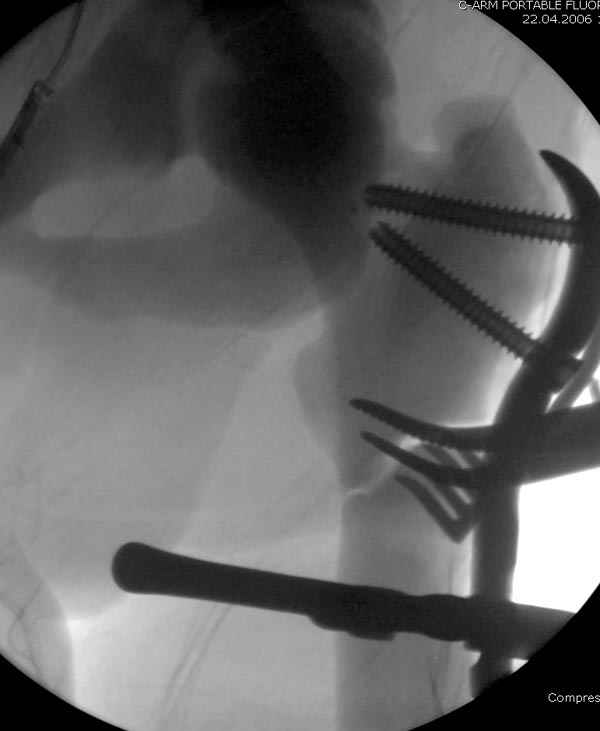

После неудачной попытки скелетного вытяжения в первом мед.учреждении, после осмотра снимков и изучения истории, поставили диагноз “Остеопетроз” или мраморная болезнь, редкая наследственная костная паталогия, где имеется нарушение формации остеокластов.

Конечно, было бы идеальным применение интрамедуллярного остеосинтеза, но учитывая прежний собственный опыт (лечил перелом бедра) и

публикации, предупреждающие о трудностях при обработке кости (иногда из-за неподготовленности инструментария результатом была неадекватная фиксация перелома, или перенос операции из-за фактора усталости оперирующего персонала), решили применить пластину (и в этом же случае был выбран Synthes plate, так что представитель за два дня

Заказаны были дополнительные различные дрели, и на следующий день, усиленной бригадой, больного прооперировали, потратив на каждое отверстие около 25-35 минут, хотя сверлили с охлаждением по нарастающей по диаметру сверл и с их заменой каждые 2 мм сверления.

Теперь стоит задача со сращением перелома, из-за отсутствия литературных данных по применению костных стимуляторов при остеопетрозе, и не зная как поведет в этой среде Grafton, все таки надеюсь, что даст толчок к стимуляцию, решил применить пастообразную деминерализованную костную матрицу, расположив спереди между отломками.